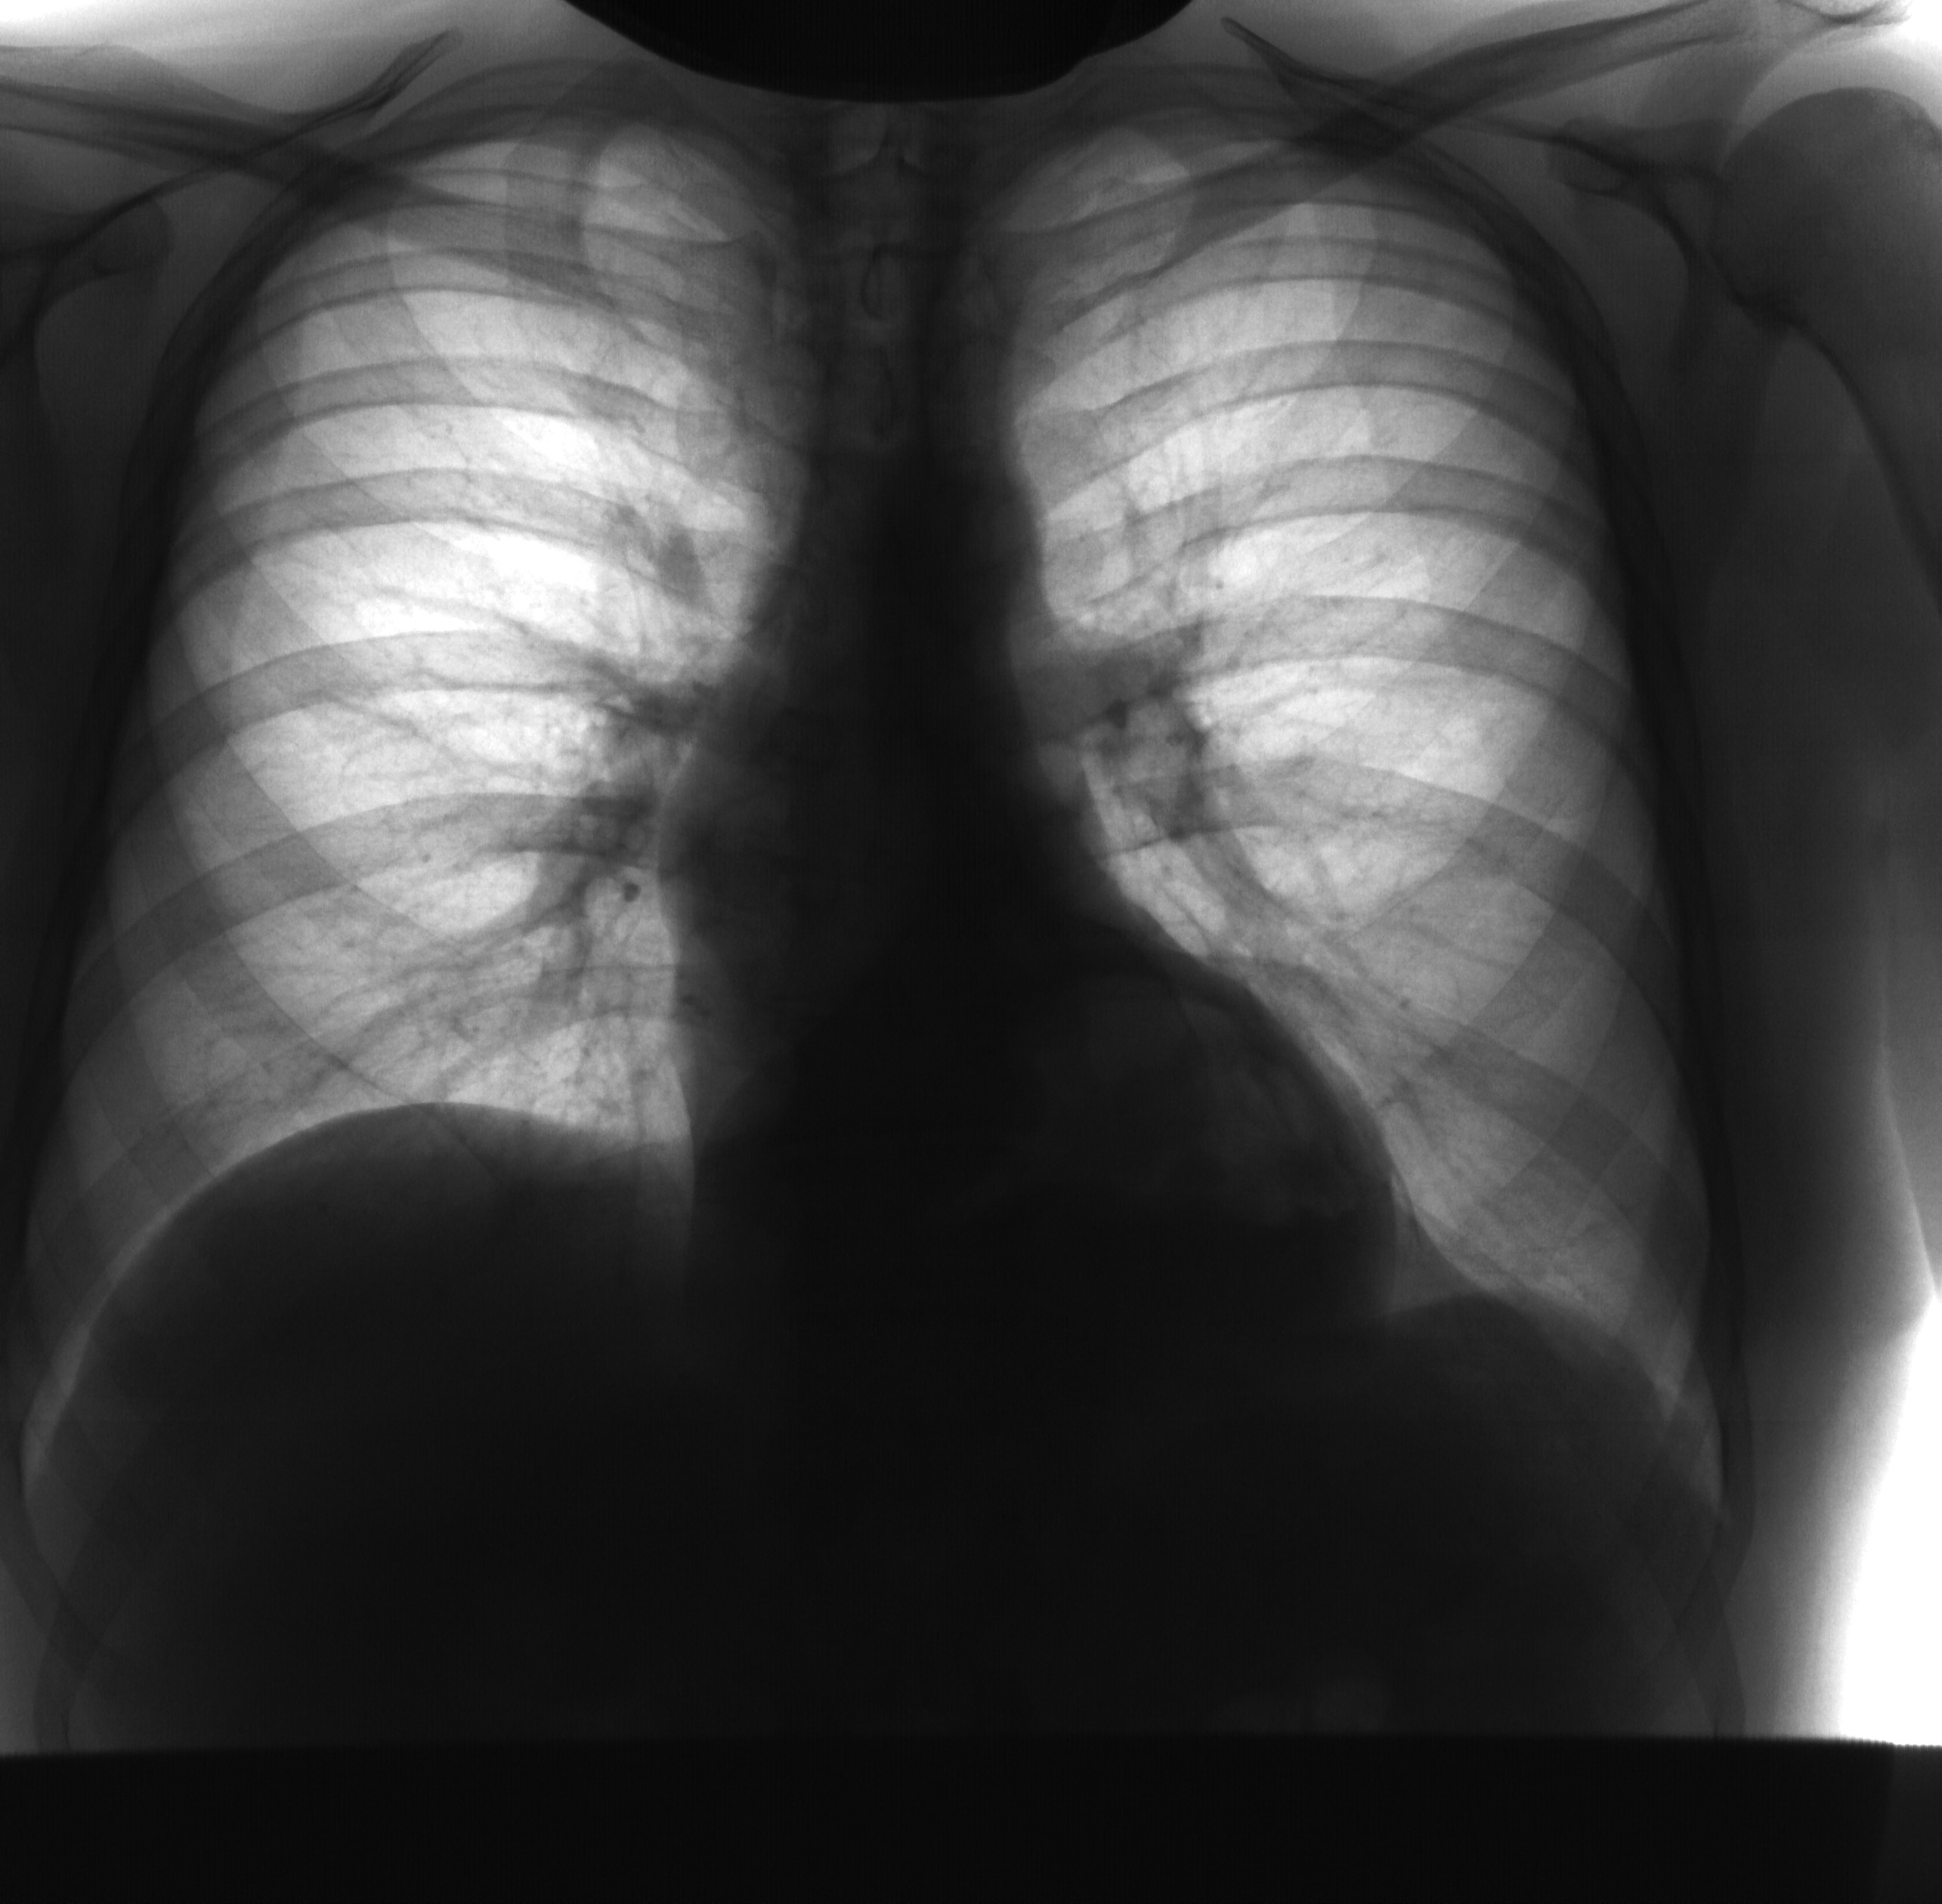

Пациенту 13 лет. Жалобы на отёки нижних конечностей, увеличение живота и массы тела за последнее время. Объективно - норм. телосложения, кожные покровы бледные, незначительную одышку при ходьбе,...